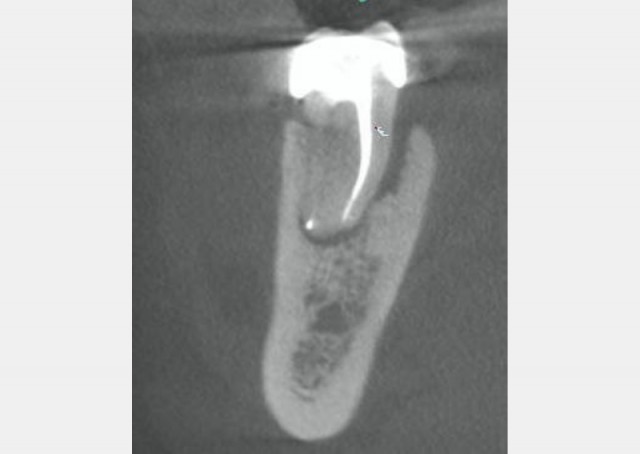

Invasive Cervical Root Resorption: The New Dental Epidemic?

Learn more about how to address invasive cervical root resorption, which is also known as extra-canal invasive root resorption, and…By Lou Berman